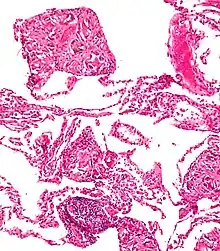

Foreign body giant cell reaction to nylon suture material

Foreign body granuloma